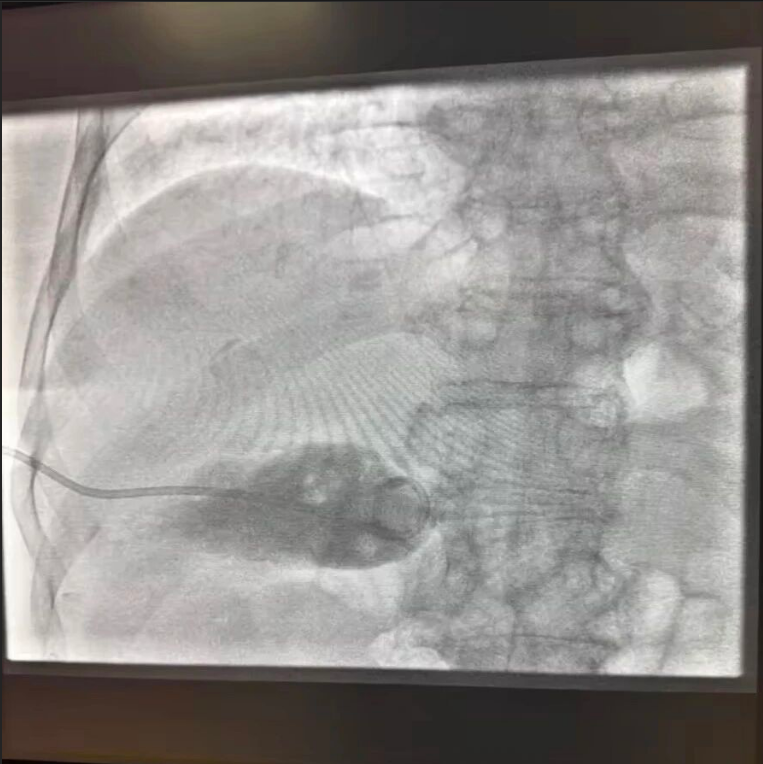

新春坚守,多学科联动更显担当。大年初一,老年病科郭伟主任团队紧急收治一名 88 岁高龄的胆囊结石合并胆囊炎患者,患者消化道症状进行性加重,基础疾病多,病情风险高。科室第一时间启动多学科会诊,普外一科刘健主任、介入科郑主任立即响应会诊请求,紧急评估病情后,于大年初五为患者急诊实施经皮经肝胆囊穿刺置管术。手术过程十分顺利,术后患者生命体征平稳,各项指标逐步恢复正常,成功为高龄老人化解急症危机。